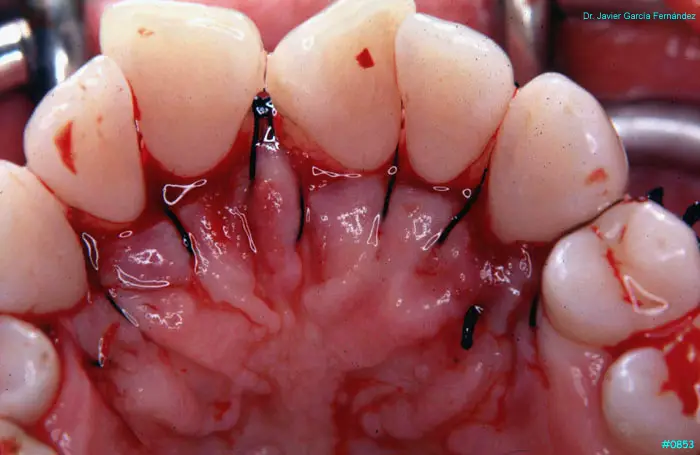

Atlas of Surgical Techniques in Periodontics. Chapter III. Atlas de Técnicas Quirúrgicas en Periodoncia